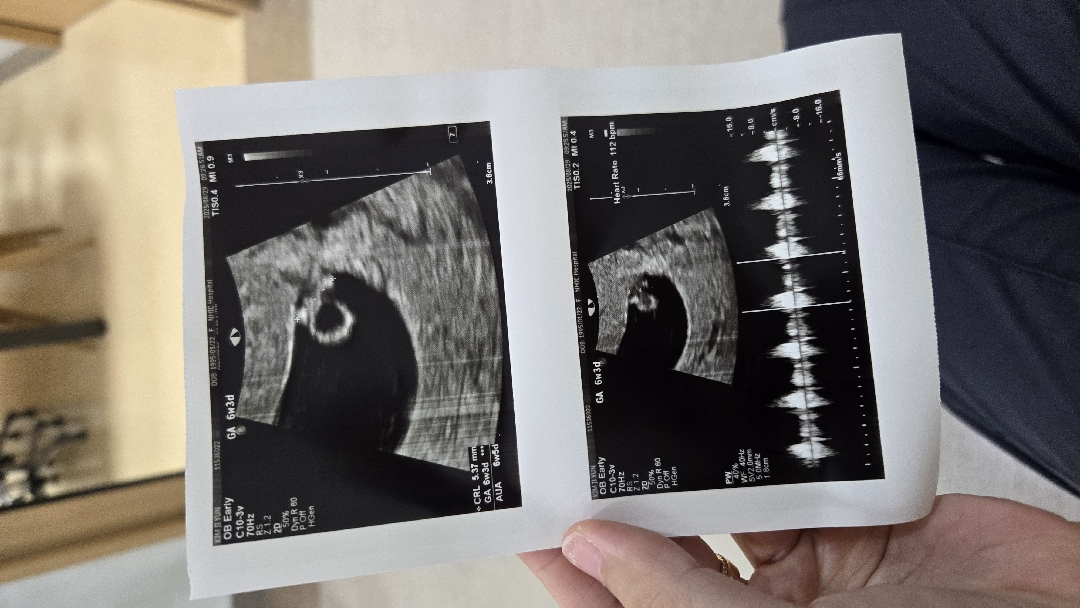

저랑 ㅎ주수예정일 하루차인데 ... 저는 6주 3일에 넘 작아서 난황만보구 심소는 못들엇는데:;;;; 부럽네영 ㅎ

미신이지만 재미로 ㅎㅎ 아들일지딸일지봐주세용 6주3일차 26년4월21일 출산예정입니당 😝

3주뒤에보고 주수가바뀔수도있다고하시더라구요! 곧심장소리들을수있으실거에요 ㅎㅎ